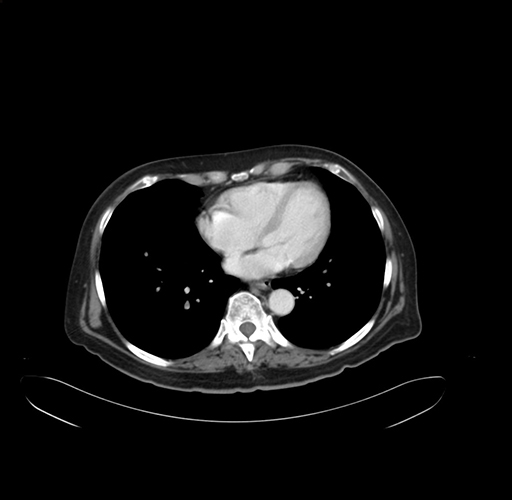

Pre-Chemo: Axial Venous